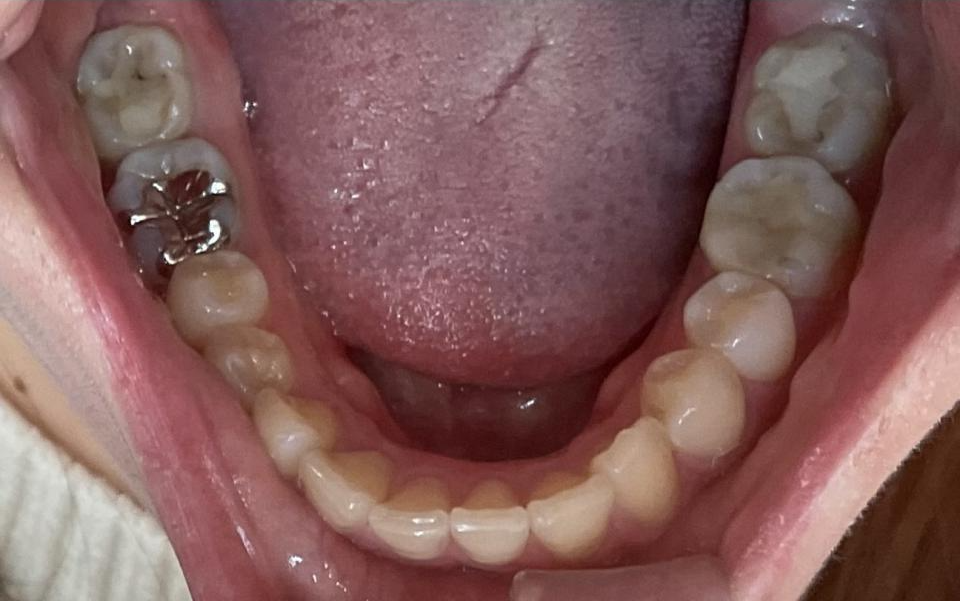

がたがた(叢生)の部分的なマウスピース矯正治療例

矯正治療後

20代女性の患者さんです。

マウスピース型の矯正治療装置を使用し、歯のやすり掛け(IPR)を行いました。

現在はマウスピース型のリテーナーで後戻りの防止をして定期的にチェックをしています。

| 矯正治療期間 | 7か月 |

| 抜歯の有無 | なし |

| 治療費 | 300000円(検査/診断/施術料含む) |

| リスク・注意点 |

歯の移動に伴い痛みを感じる場合がある 治療後保定装置を使わないと後戻りを生じる |